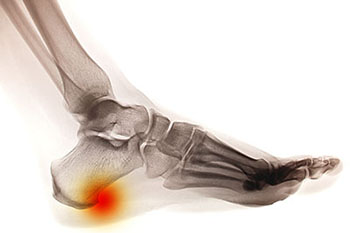

Heel spurs are deposits of calcium that build upon the underside of the heel bone. They are usually caused by excessive strain on the foot muscles and ligaments and are especially common among athletes. Other risk factors for developing heel spurs include being overweight or obese, wearing ill-fitting shoes, and having an abnormal gait or walking pattern.

Heel spurs are typically diagnosed through a physical examination and imaging studies like X-rays. Treatment recommendations may include doing certain foot stretches, modifying your footwear, wearing orthotics, or using night splints. Over-the-counter medications can be used to relieve pain and inflammation. Surgical treatment may be considered if more conservative measures have failed to alleviate your symptoms, but surgery is rarely required for heel spurs.